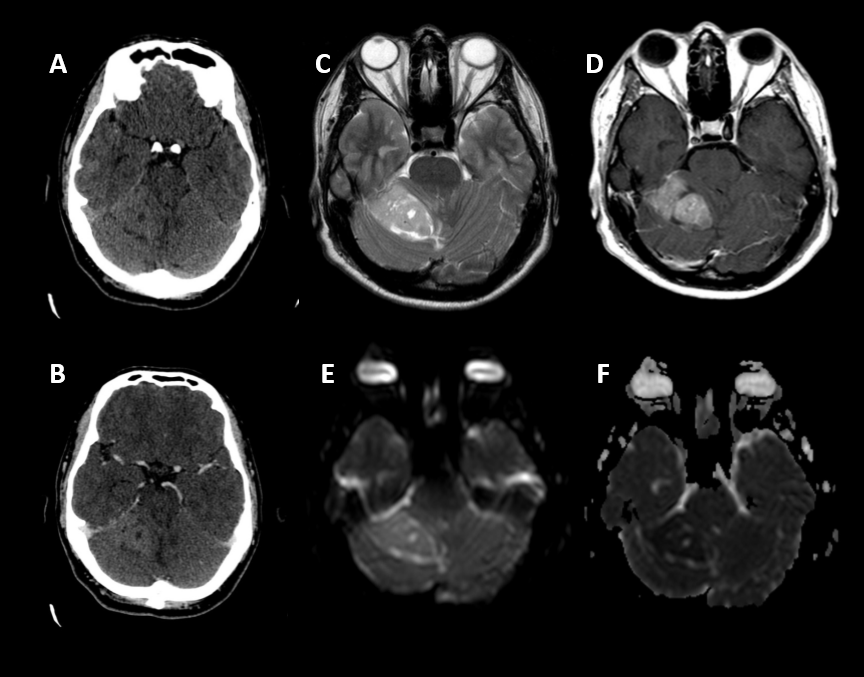

FIGURA1:

A. B. TC cráneo basal y con contraste:  lesión expansiva intraaxial en hemisferio cerebeloso derecho, levemente hiperdensa en TC basal con realce heterogéneo a expensas de áreas quísticas/necróticas en su interior y mínimo edema perilesional

C. D. E. F. RM cráneo, plano axial. Secuencias FSE T2, T1 con gadolinio y  difusión, que muestran heterogeneidad de señal T2 a expensas de áreas quísticas, sin edema perilesional, realce heterogéneo de contraste y marcada restricción de difusión con unos valores ADC muy disminuidos